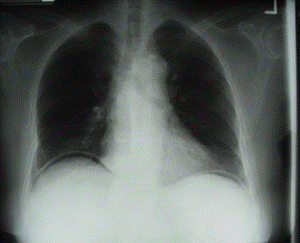

What Are Enlarged Mediastinal Lymph Nodes?